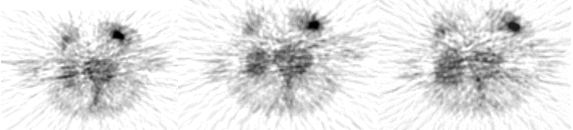

Các hình ảnh PET (cắt ngang) với các thời gian khác nhau sau điều trị để đánh giá điều trị cho thấy ít thay đổi hoạt độ PX. KL: Không đáp ứng điều trị

Hình ảnh PET/CT cho thấy giảm hoạt độ PX theo thời gian sau ĐT. KL: Có đáp ưng với điều trị

Hình ảnh PET/CTtrước và sau điều trị cho thấy  hoạt độ PX giảm rõ rệt. KL: Có đáp ưng với điều trị